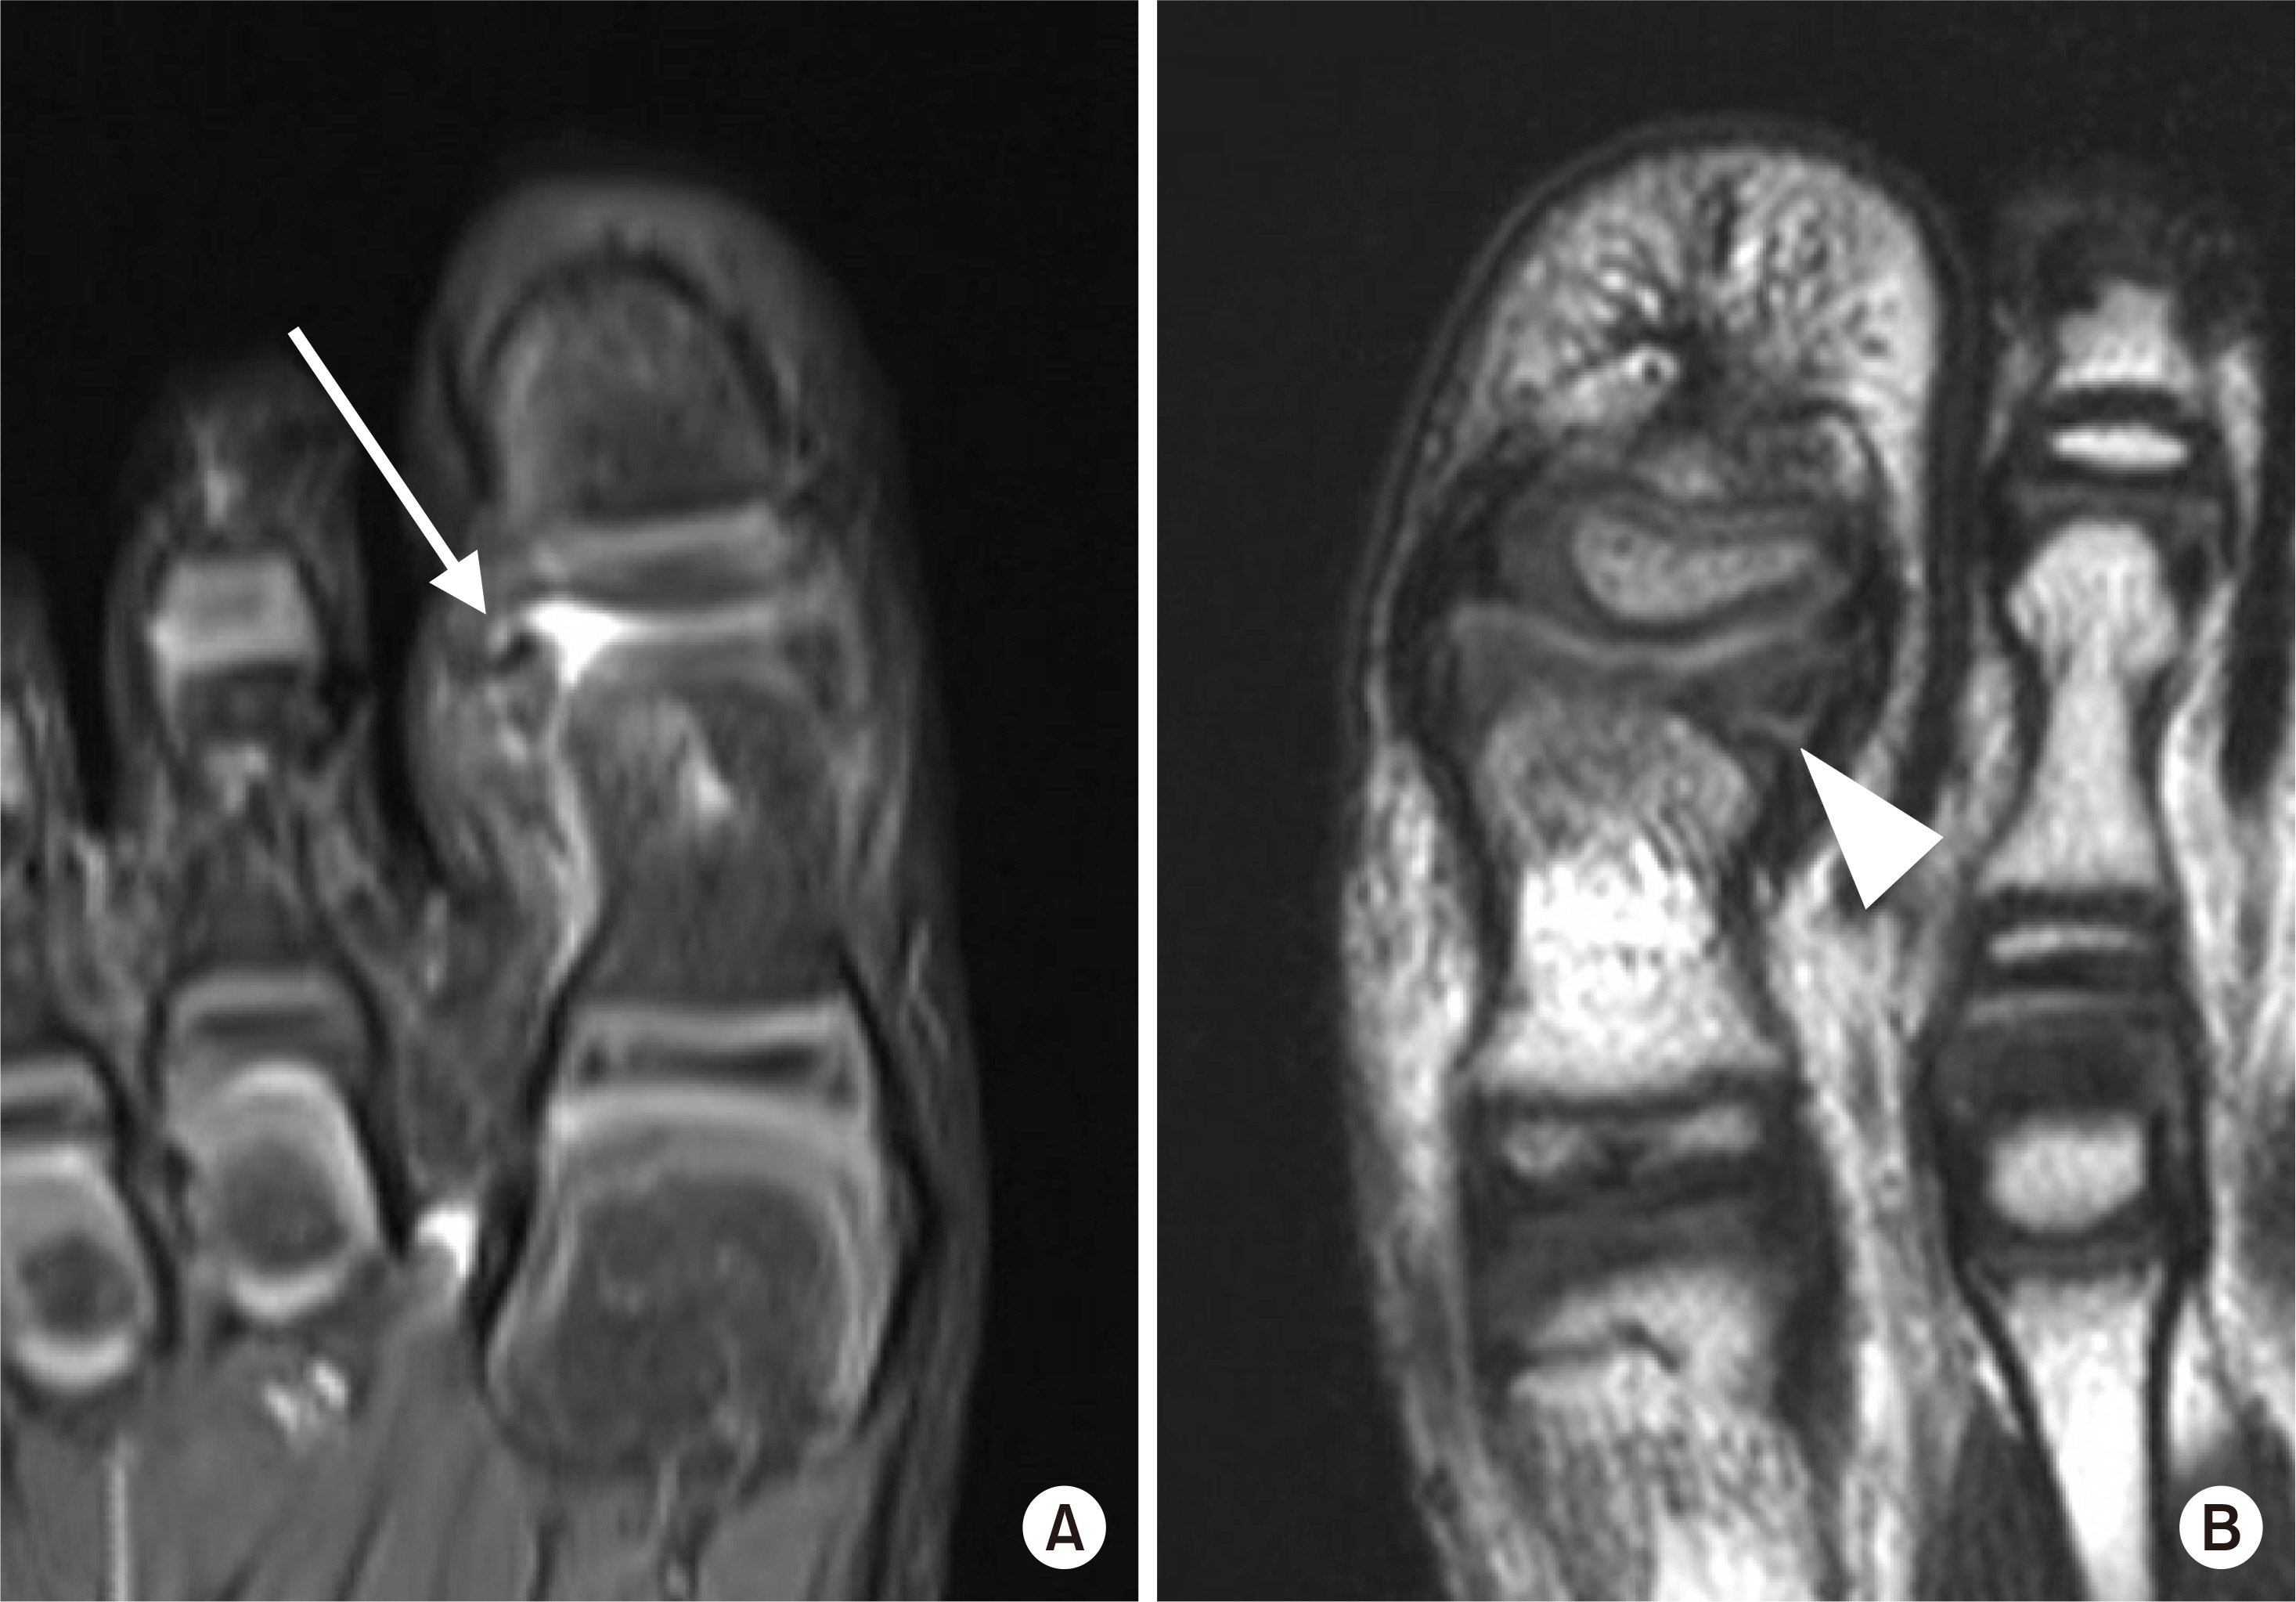

Fig. 2.

(A) Rotation of the osteochondral fragment (arrow). (B) Entrapment of the periosteum in the fracture site (arrowhead).